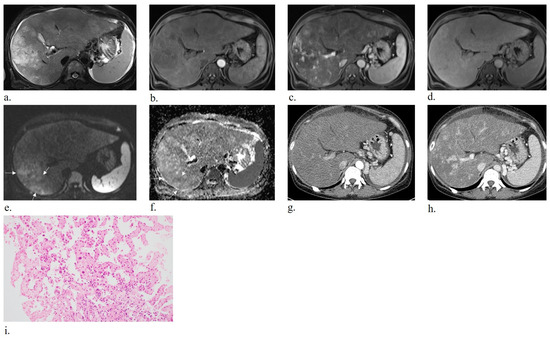

Primary Hepatic Angiosarcoma: Distinct Imaging Phenotypes Mirroring Histopathologic Growth Patterns in a Retrospective Human Study

Background/Objectives: To date, no studies have examined radiologic findings by histologic patterns of primary hepatic angiosarcoma; this study clarified radiologic findings of primary hepatic angiosarcoma according to distinct histologic patterns. Methods: From January 2010 to October 2024, 17 individuals (mean age, 69 years ± 11; 11 men) with pathologically confirmed primary hepatic angiosarcoma underwent computed tomography (CT) with or without magnetic resonance imaging (MRI). Histologic patterns were classified as mass-forming, subdivided into vasoformative and non-vasoformative (epithelioid and spindled) patterns, or non-mass-forming, subdivided into sinusoidal and peliotic patterns. Two radiologists independently reviewed CT and MRI images, classifying lesions as non-mass-forming or mass-forming. Hypervascular portions and targetoid patterns were also assessed. Associations between histologic patterns and radiologic findings were evaluated using Fisher’s exact test. Results: Mass-forming tumors were observed in 13 individuals (76.5%), and non-mass-forming tumors in 4 individuals (23.5%). Significant correlation (p < 0.05) was found between radiologic classification (non-mass-forming or mass-forming) and corresponding pathologic patterns. Pathologic subdivision into vasoformative and non-vasoformative patterns did not correlate with hypervascular portions on imaging. Conclusions: Pathological classification into mass-forming and non-mass-forming patterns corresponds closely to radiologic classification of mass-forming and non-mass-forming lesions, indicative of strong pathologic features in imaging. Full article

Show Figures

Figure 1